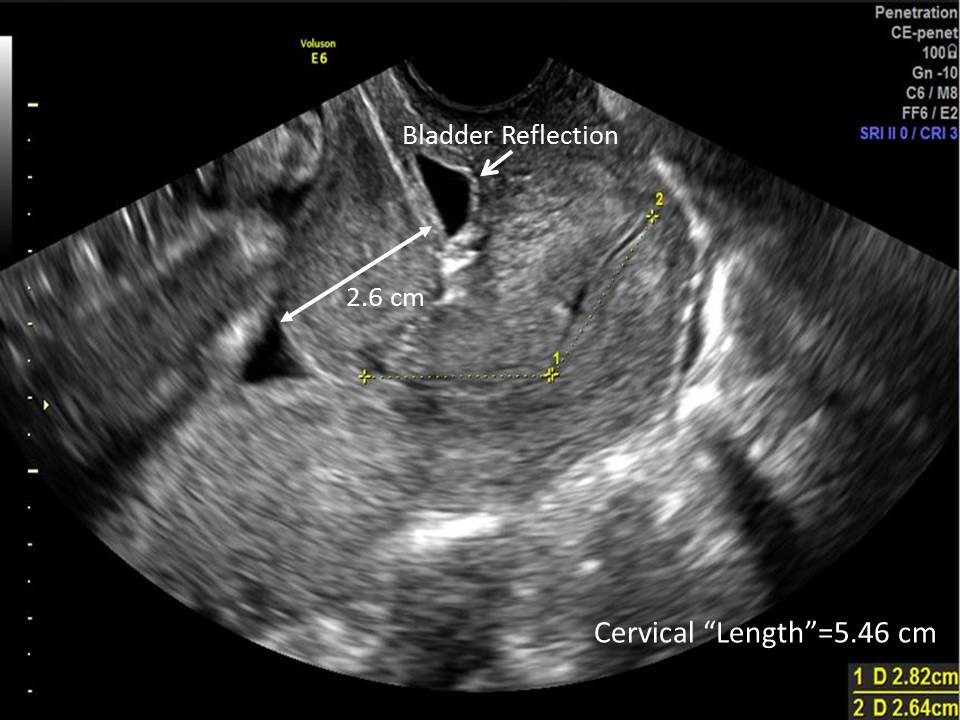

- Poorly-developed lower segment (PDLUS), or cervical isthmus, is characterized by a long “cervix” (> ~5 cm), S-shaped canal, different echogenicties in the “cervix”, increased bladder-to-amniotic cavity distance, and “internal os” cephalad to the inferior edge of the bladder reflection (Figure 1).

Figure 1. Poorly-developed lower uterine segment.